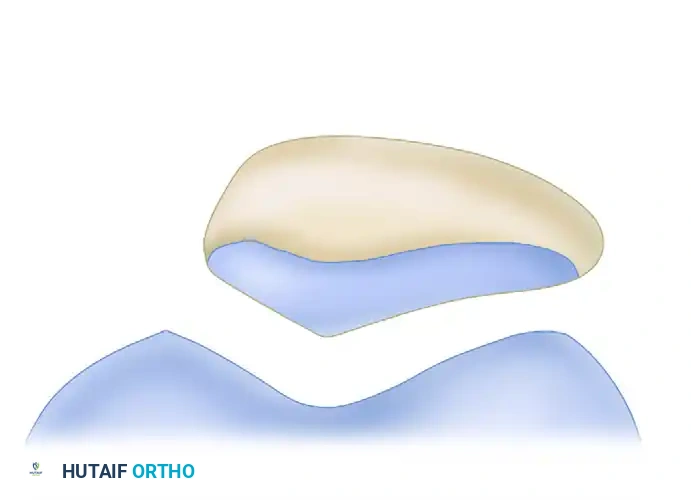

Assessing Patellar Tilt and Sulcus Morphology

Once the appropriate views are obtained, the surgeon must analyze the images for signs of malalignment, tilt, and dysplasia.

On an axial or skyline view, the patella should sit symmetrically within the trochlea. A lateral tilt indicates tightness of the lateral retinaculum and potential insufficiency of the medial restraints.

Trochlear Dysplasia and Sulcus Angle:

The morphology of the femoral sulcus is a primary determinant of patellar stability. While complex classification systems (such as the Dejour classification) exist, under most circumstances, simply evaluating the radiographs is sufficient to differentiate a shallow, dysplastic sulcus from a normal, deep sulcus. The Merchant view is particularly useful for demonstrating a wide, flattened sulcus angle, which predisposes the patient to lateral subluxation.

Patellofemoral Congruence and Measurements

An analysis of patellofemoral congruence is highly indicated, especially when clinical subluxation is minimal or subtle. The measurements described by Merchant et al. remain the gold standard for quantifying patellar subluxation.

FIGURE 47-10: Measurements of patellofemoral congruence described by Merchant et al. F, facet; L, lateral condyle; M, medial condyle; P, patellar ridge; S, sulcus. Angle MSL is the sulcus angle (average, 137 degrees; standard deviation, 6 degrees). Line SO is the zero reference line bisecting the sulcus angle. Angle PSO is the congruence angle (average, −8 degrees; standard deviation, 6 degrees). Line PF (lateral facet) and line ML form the patellofemoral angle, which should diverge laterally.

Pitfall: A congruence angle greater than +16 degrees is highly indicative of pathologic lateral patellar subluxation. Failure to recognize an abnormal congruence angle may lead to inappropriate clearance for sports, resulting in recurrent dislocation and progressive chondral damage.